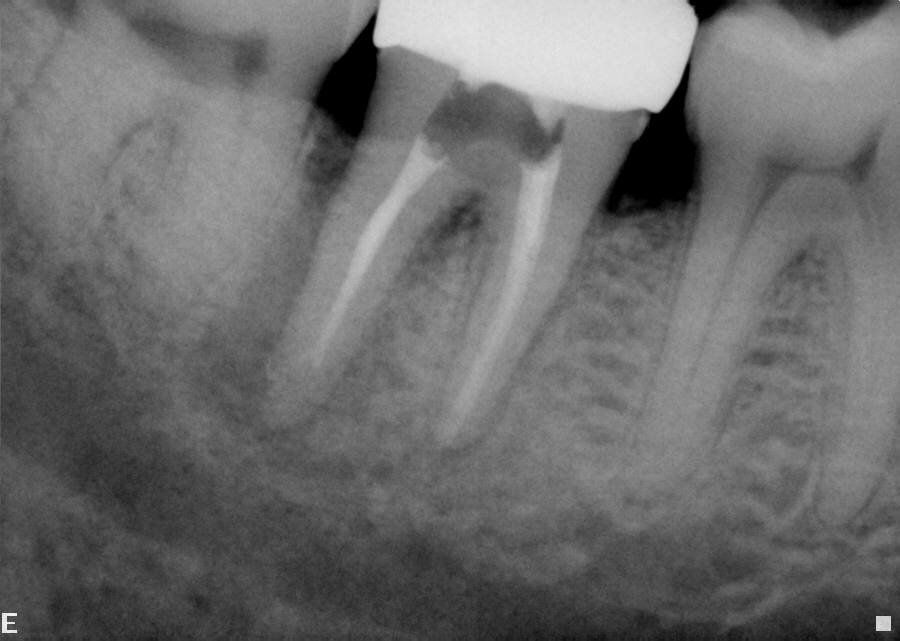

A functional, asymptomatic tooth with no clinical signs of pathosis can be considered successful even without complete healing of the ligament.Endodontic success has traditionally been defined as the prevention or elimination of periapical disease following root canal treatment, meaning both complete healing of the PDL radiographically and absence of symptoms clinically. However, utilizing CBCT to evaluate PDL healing Patel showed a 25% reduction in "success" compared to periapical radiographs. Many of these teeth are still in function, asymptomatic, free of active disease, and esthetic; yet fail to meet the above, very stringent, definition of endodontic success. Has treatment been unsuccessful in these cases? How do we measure success clinically? Does it really even matter what definition we use for “success”? Having a clear definition of success is important because treatment plans are be based largely on the prognosis of treatment options. Endodontic treatment and implant placement will frequently be compared, however most implant studies define success as simply survival of the implant. (Iqbal) Helping patients maintain their natural dentition is a primary goal of endodontics, and a definition of success that emphasizes survival more closely aligns with both patient goals and allows for the most accurate comparison of treatment options. Doyle addressed this discrepancy directly by analyzing both the success and survival of implant and endodontic treatment, which resulted in almost identical success and survival rates. A financial evaluation, however, shows that in most circumstances endodontic treatment is the most cost effective option. (Pennington)